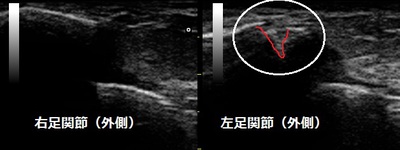

川越市 主婦 左足関節の痛み 腓骨裂離損傷

川越市 60代主婦。 左足関節の痛み、 腓骨裂離損傷。

【原因】

自宅近くを歩行中に道路の段差に足が引っかかって左足関節を思いっきり捻ってしまいました。

その日の夜に近隣の接骨院で捻挫と言われました。特に固定もしてもらいませんでした。

2日後に当院へ来院されて超音波検査の結果、左の腓骨の一部が靭帯に引っ張られて裂離(剥離)

し、靭帯も部分断裂していることが認められました。

【治療】

腓骨の裂離部と靭帯損傷の修復を促進させる特殊な電気療法を行います。施術後はテーピングと

足関節用のサポーターでしっかりと固定します。

この固定でギプスを巻かずに済み、毎日患部の施術が出来るので治癒も早まります。ねんざと思っても

骨や軟骨の損傷が隠れている場合がありますので、当院では超音波(エコー)検査で患部の状態を

画像で評価しています。